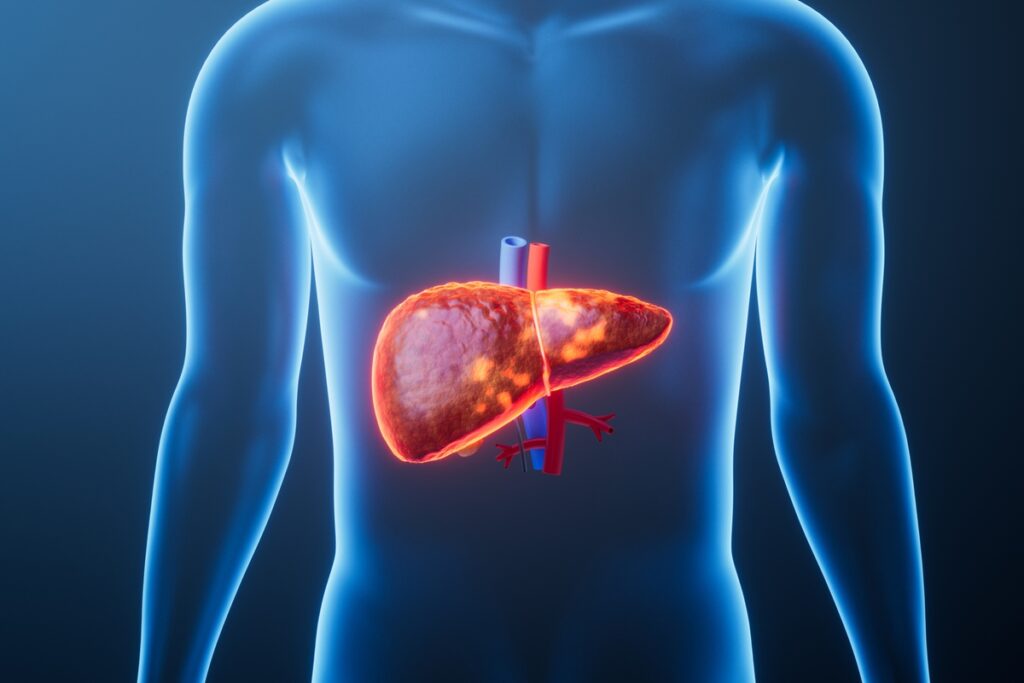

Após o consumo de altas doses de cerveja, vodca, tequila, espumante, vinho, entre outras bebidas alcoólicas, na virada do ano, o corpo pode dar “tilt”. Entre os órgãos mais afetados pela ingestão exagerada de álcool, consta o fígado, glândula responsável por metabolizar substâncias e desintoxicar o organismo.

O consumo de bebidas alcoólicas causa estresse às células do fígado

O fígado é responsável pela desintoxicação do organismo

O fígado é prejudicado pelo consumo exagerado de bebidas alcoólicas

O fígado é o órgão que metaboliza as substâncias ingeridas e, por isso, sofre os efeitos do consumo excessivo de bebidas alcoólicas